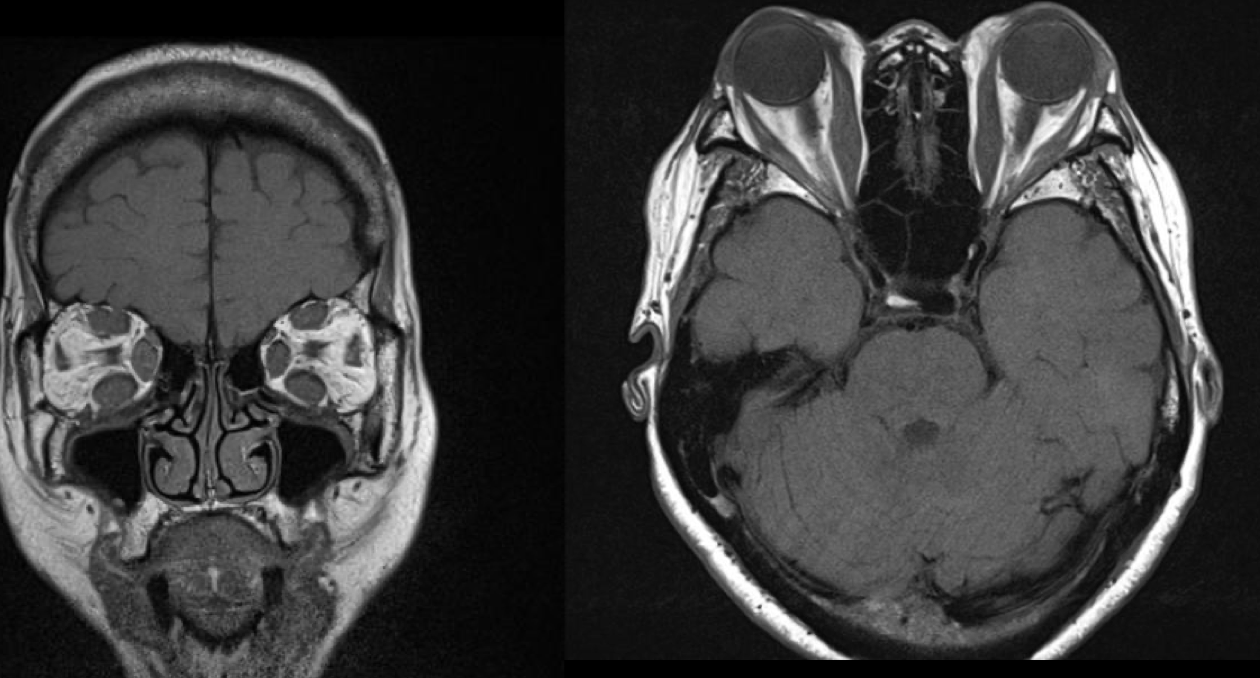

Agrandamiento de los músculos extraoculares

Exoftalmos

Nervio óptico estirado

TC en Orbitopatia tiroidea